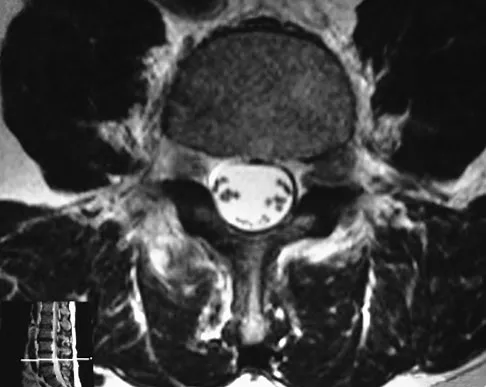

Figures 28a through 28c show the MRI scans of a 30-year-old woman who weighs 290 lb and has low back and left leg pain. She also reports frequent urinary dribbling, which her gynecologist has advised her may be related to obesity. Examination will most likely reveal

Explanation